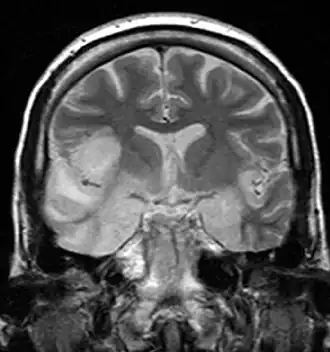

Ressonância magnética de paciente com encefalite por vírus do herpes simples em que se observa alto sinal nos lobos temporais e no giro frontal inferior

Hemorragia também é incomum, porém encontrada nas encefalites por Herpes e por amebas. Ressonância magnética oferece melhor resolução, mas o diagnóstico é clínico: paciente com febre, vômitos, alteração da consciência ou do comportamento devem ser investigados para encefalites sem perda de tempo. Em pacientes com encefalite por herpes simples, o eletrencefalógrafo pode mostrar ondas afiadas em um ou ambos os lóbulos temporais.